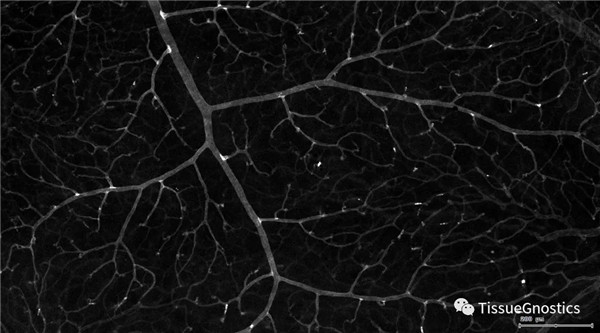

單通道灰階圖(↑:FITC,↓:Texa Red)

血管識別:根據Texa Red通道進行識別,并去除面積小的及非同一焦面的血管,僅對確定的清晰的同一焦面的大血管進行面積統計。

血管與小膠質細胞的距離

血管與小膠質細胞的距離0-0.1μm(紅色框線標記)

血管與小膠質細胞的距離0.1-1μm(粉色標記)

血管與小膠質細胞的距離1-3μm(粉色標記)